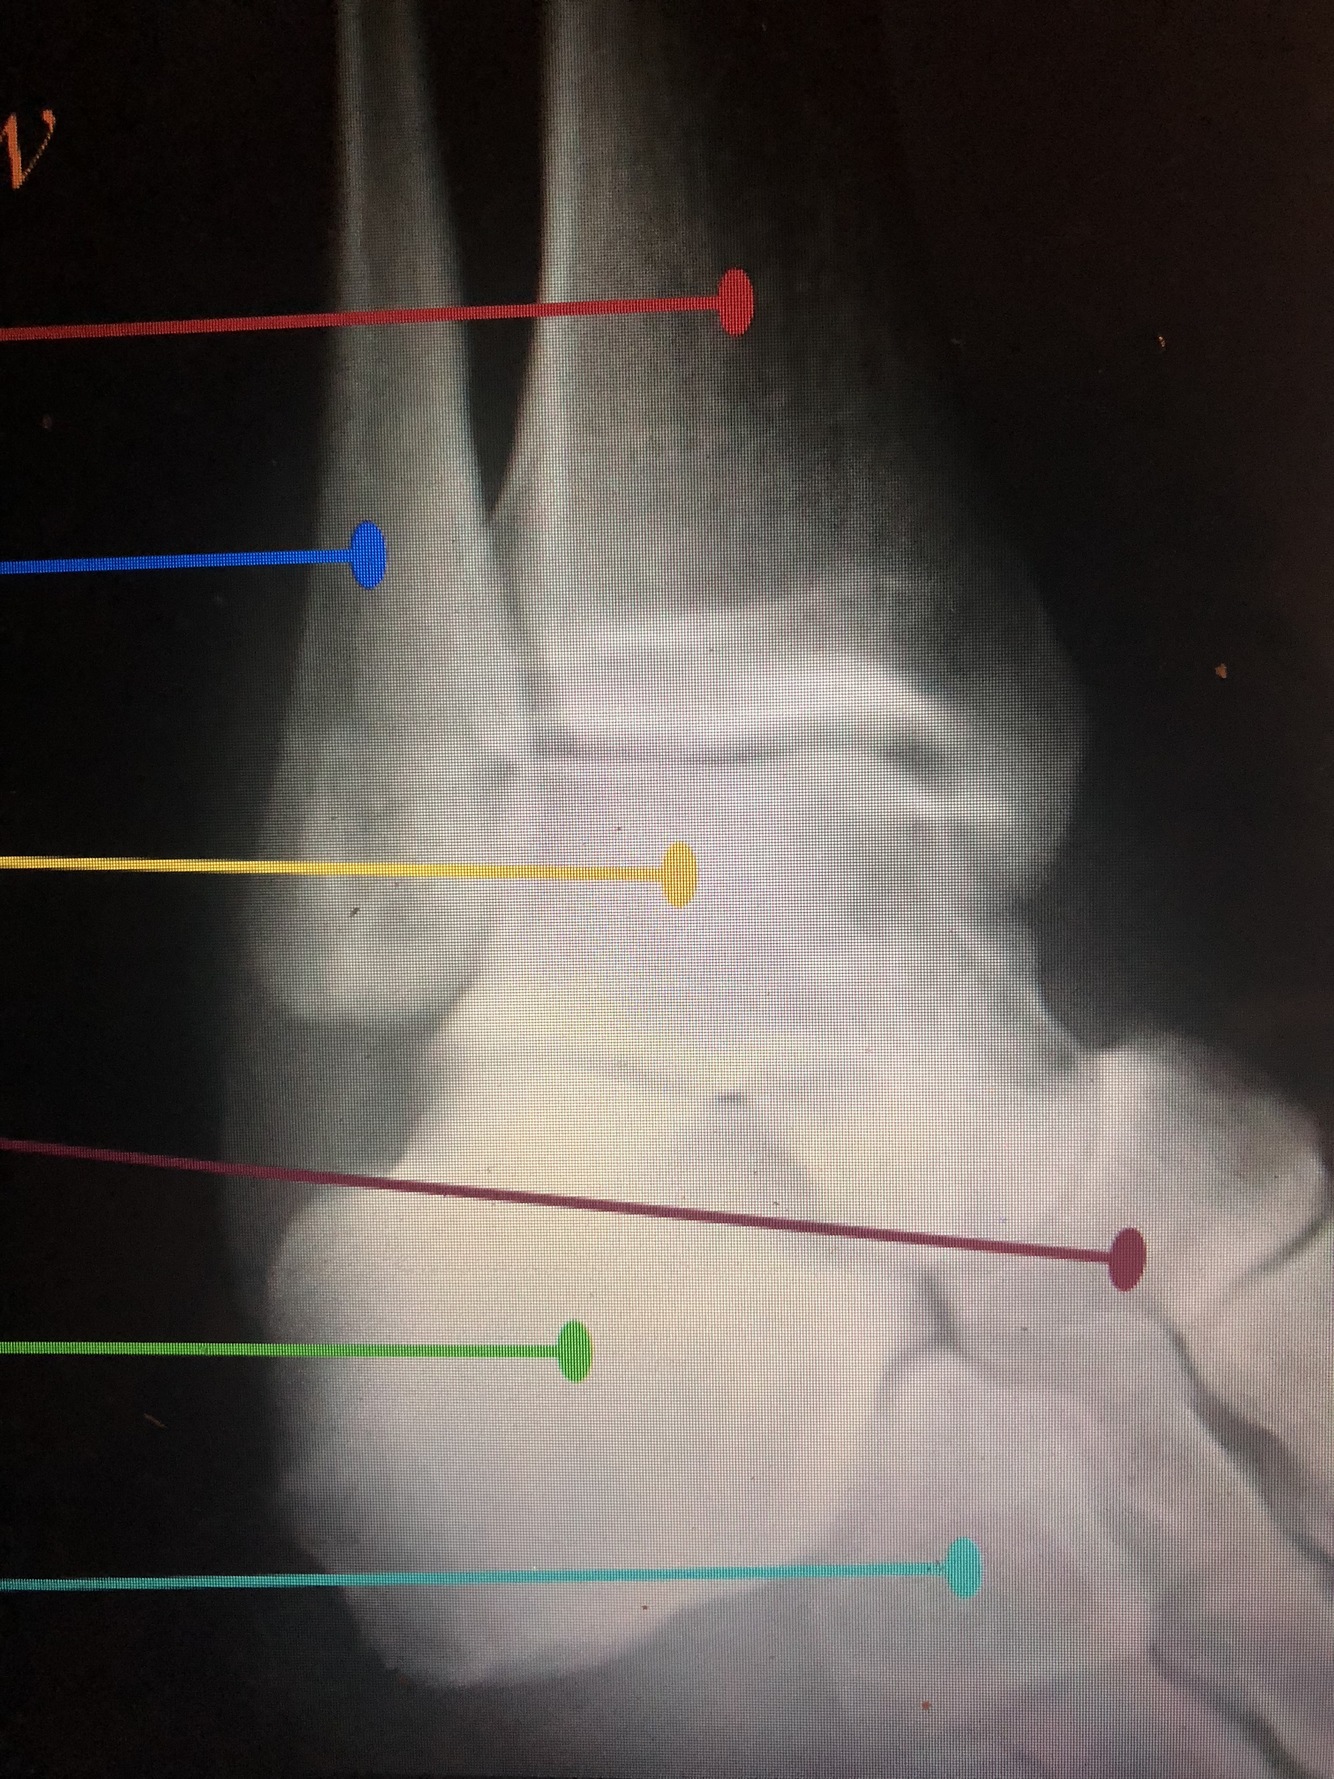

What bone is yellow?

Talus

What bone is brown?

Navicular

What bone is light green?

Calcaneus

What bone is light blue?

Cuboid